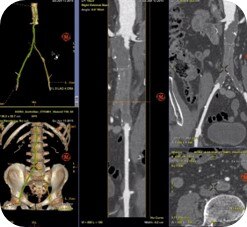

Planifier

Guider

Évaluer